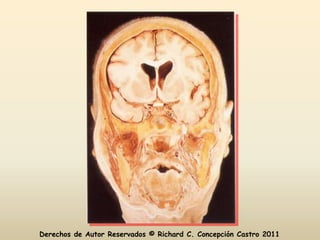

Diseccionar

Diseccionar Derechos de AutorReservados © Richard C. Concepción Castro 2011